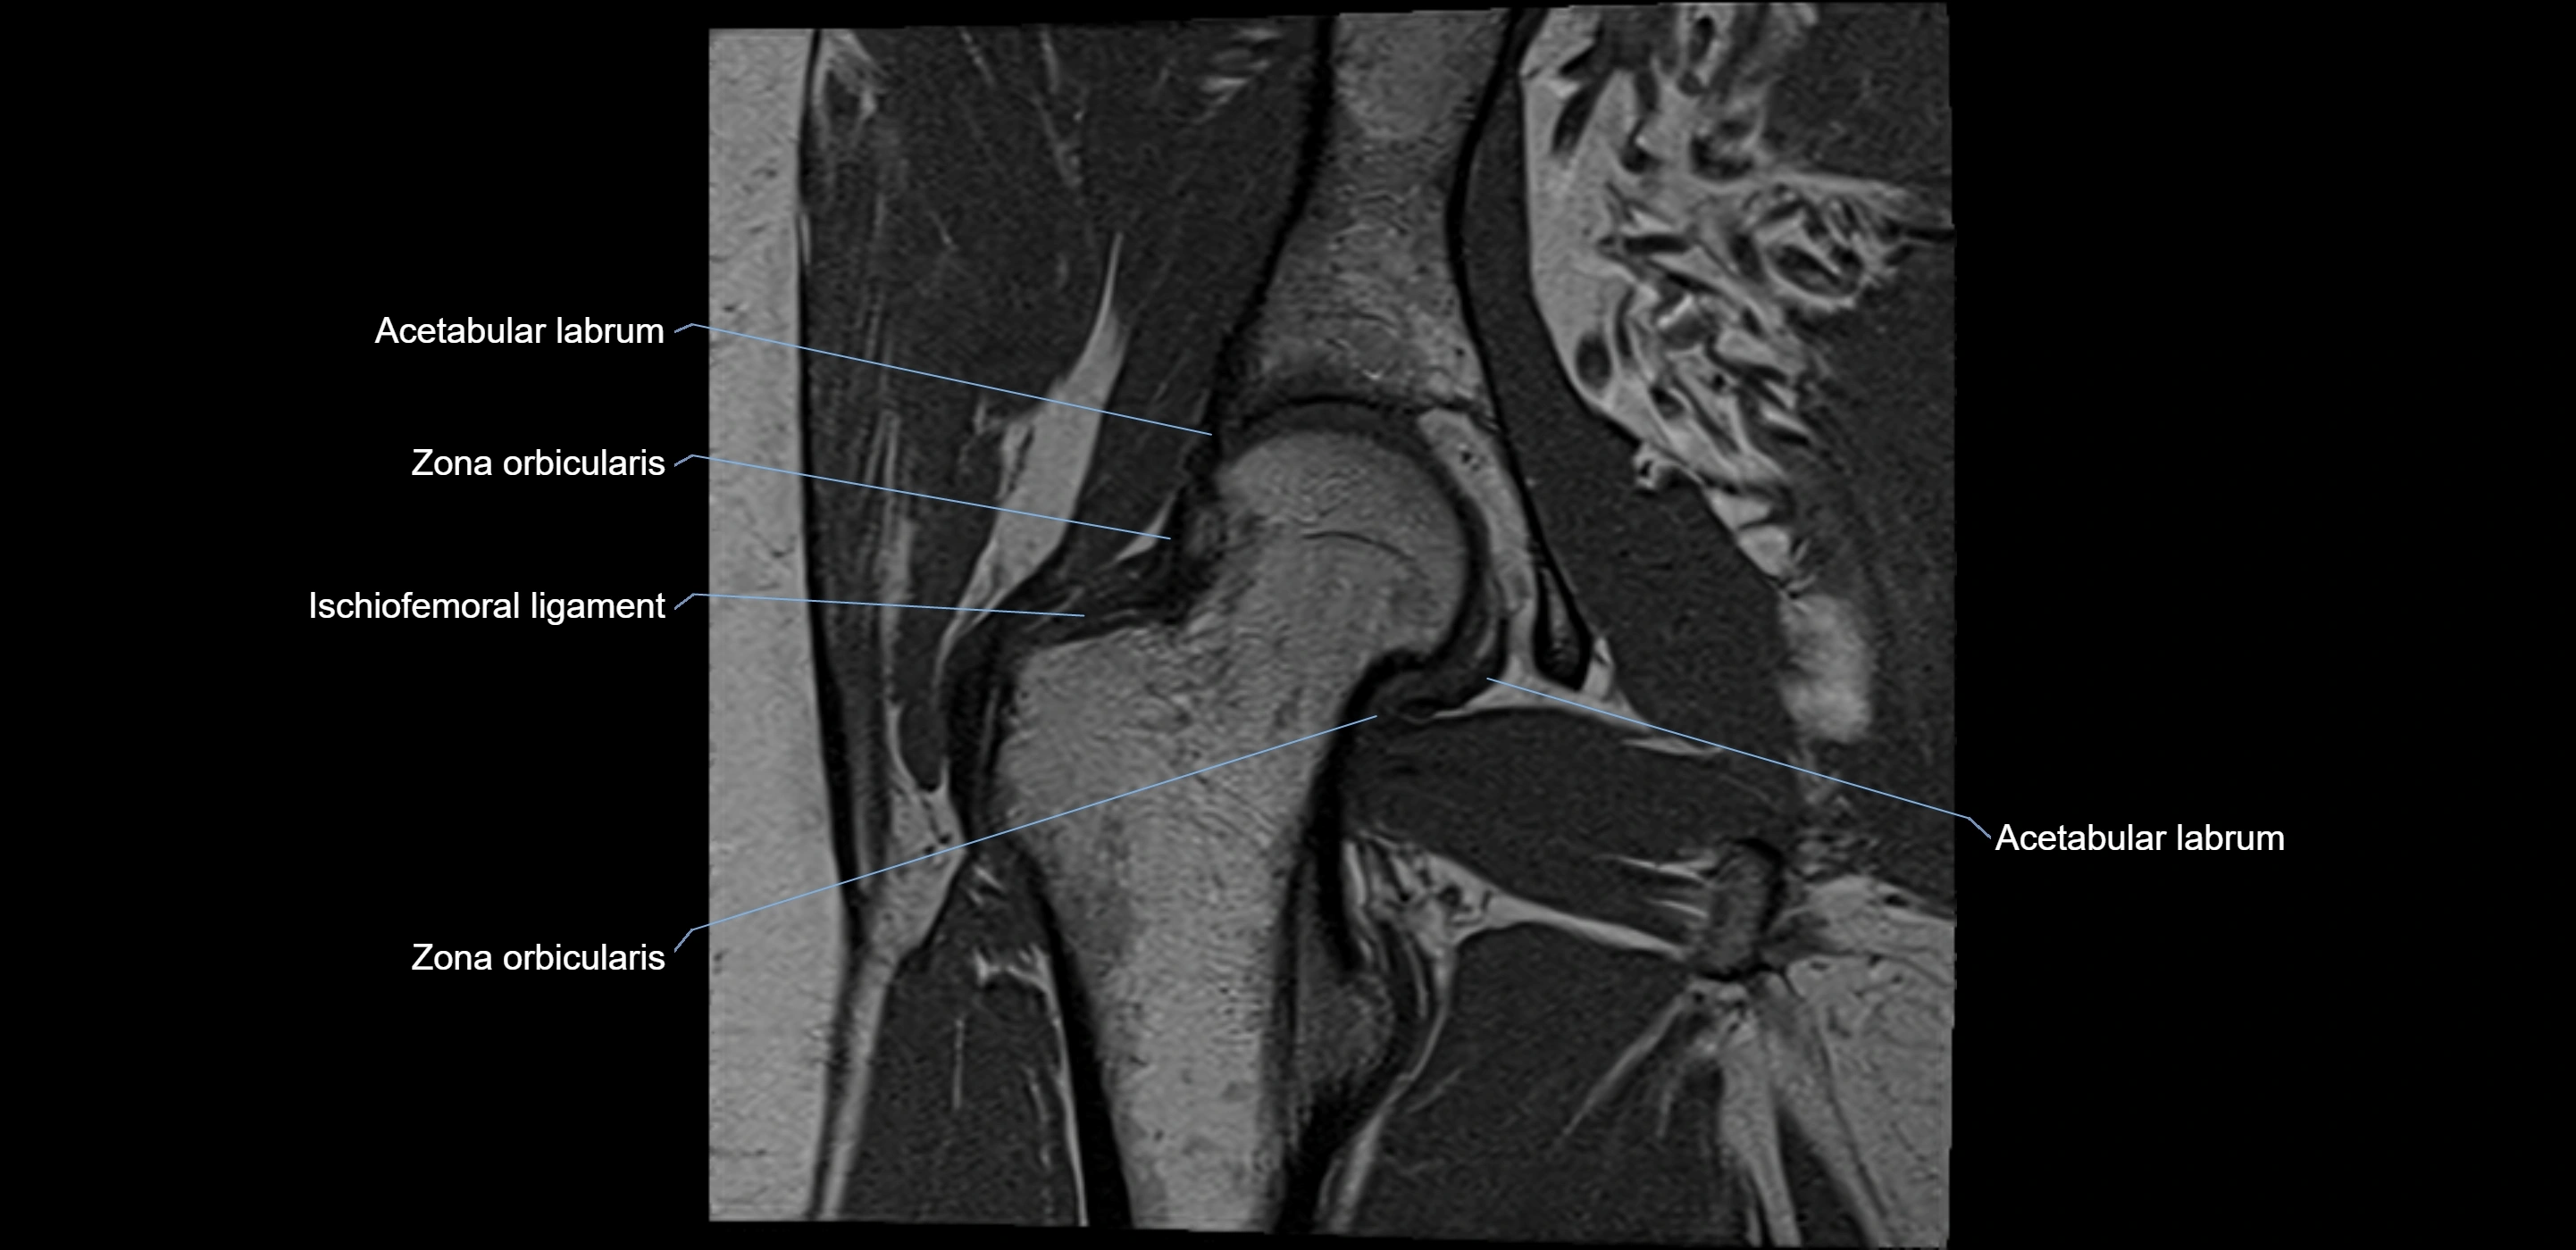

The acetabular labrum is a fibrocartilaginous ring that surrounds the rim of the acetabulum in the hip joint. It deepens the hip socket, increases joint stability, and maintains a suction seal that preserves negative intra-articular pressure. Structurally, the labrum transitions from hyaline cartilage of the acetabulum to dense fibrocartilage at its free edge.

It is triangular in cross-section, with its base attached to the acetabular rim and its apex projecting toward the femoral head. The labrum is most robust superiorly and anteriorly, where load bearing is greatest, and relatively thinner inferiorly.

Structure and Relations

• Superior and anterior labrum: thickest portions, stabilizing against anterior dislocation

• Inferior labrum: blends with the transverse acetabular ligament bridging the acetabular notch

• Lateral: hip joint capsule

MRI Appearance

T1-weighted images:

• Labrum: low signal intensity (dark)

• Surrounded by intermediate signal joint fluid (bright on arthrogram)

• Tears: linear or focal areas of intermediate-to-high signal interrupting labral continuity

T2-weighted images:

• Joint fluid: bright, making labral tears visible as fluid extending into or around labrum

• Degeneration: may show areas of increased signal within labrum